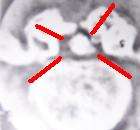

CT scan showing two views of L4-5 disc herniation

A report from Spain noted that the investigation and development of new techniques for instrumented surgery of the spine is not free from conflicts of interest. The influence of financial forces in the development of new technologies and its immediate application to spine surgery, shows the relationship between the published results and the industry support. Authors who have developed and defended fusion techniques have also published new articles praising new spinal technologies. The author calls spinal surgery the "American Stock and Exchange" and "the bubble of spine surgery". The scientific literature doesn't show clear evidence in the cost-benefit studies of most instrumented surgical interventions of the spine compared with the conservative treatments. It has not been yet demonstrated that fusion surgery and disc replacement are better options than the conservative treatment. It's necessary to point out that at present "there are relationships between the industry and back pain, and there is also an industry of the back pain". Nonetheless, the "market of the spine surgery" is growing because patients are demanding solutions for their back problems. The tide of scientific evidence seems to go against the spinal fusions in the degenerative disc disease, discogenic pain and in specific back pain. After decades of advances in this field, the results of spinal fusions are mediocre. New epidemiological studies show that "spinal fusion must be accepted as a non proved or experimental method for the treatment of back pain". The surgical literature on spinal fusion published in the last 20 years establishes that instrumentation seems to slightly increase the fusion rate and that instrumentation doesn't improve the clinical results in general. We still are in need of randomized studies to compare the surgical results with the natural history of the disease, the placebo effect, or conservative treatment. The European Guidelines for lumbar chronic pain management show "strong evidence" indicating that complex and demanding spine surgery where different instrumentation is used, is not more effective than a simple, safer and cheaper posterolateral fusion without instrumentation. Recently, the literature published in this field is sending a message to use "minimally invasive techniques"; - the abandonment of transpedicular fusions. Surgery in general, and usage of metal fixation should be discarded in most cases.[225]